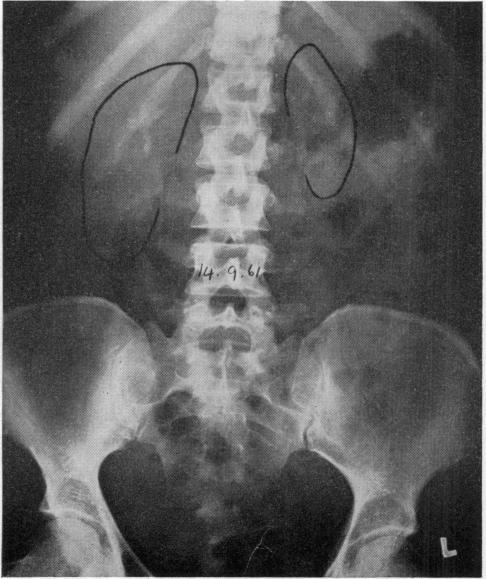

An Unusual Case of Renal Failure and Hypertension.

Br Med J. 1963 Jul 20;2(5350):167-70.